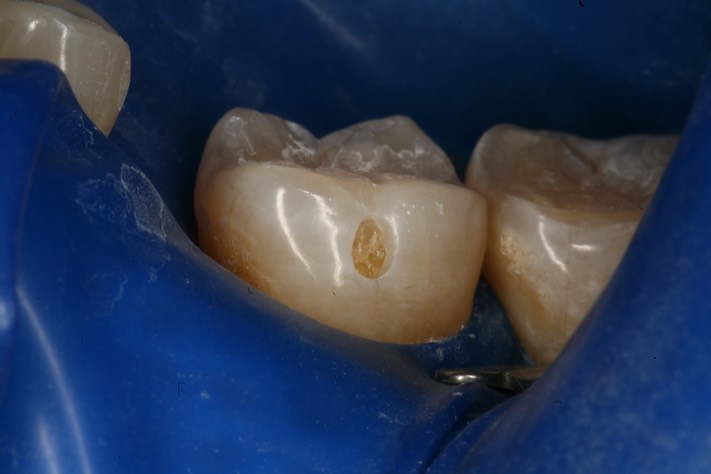

Mark Chun #18 prep